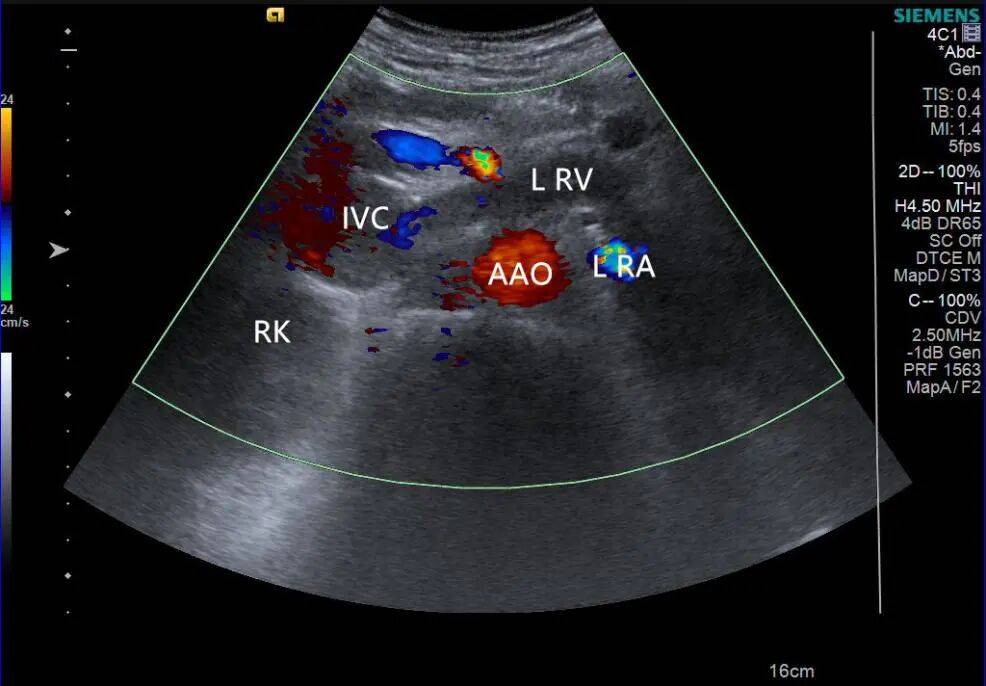

2. 左肾静脉增宽,前后径约 16 mm,其内充满低回声,下腔静脉增宽,前后径约 29 mm,其内充满低回声,向上延伸至右心房入口处。CDFI:左肾静脉、下腔静脉及其内低回声见星点状血流信号(图 3、4)。

图 4 彩色多普勒超声示低回声内见星点状血流信号( RK 右肾 IVC 下腔静脉 L RV 左肾静脉 L RA 左肾动脉 AAO 腹主动脉)